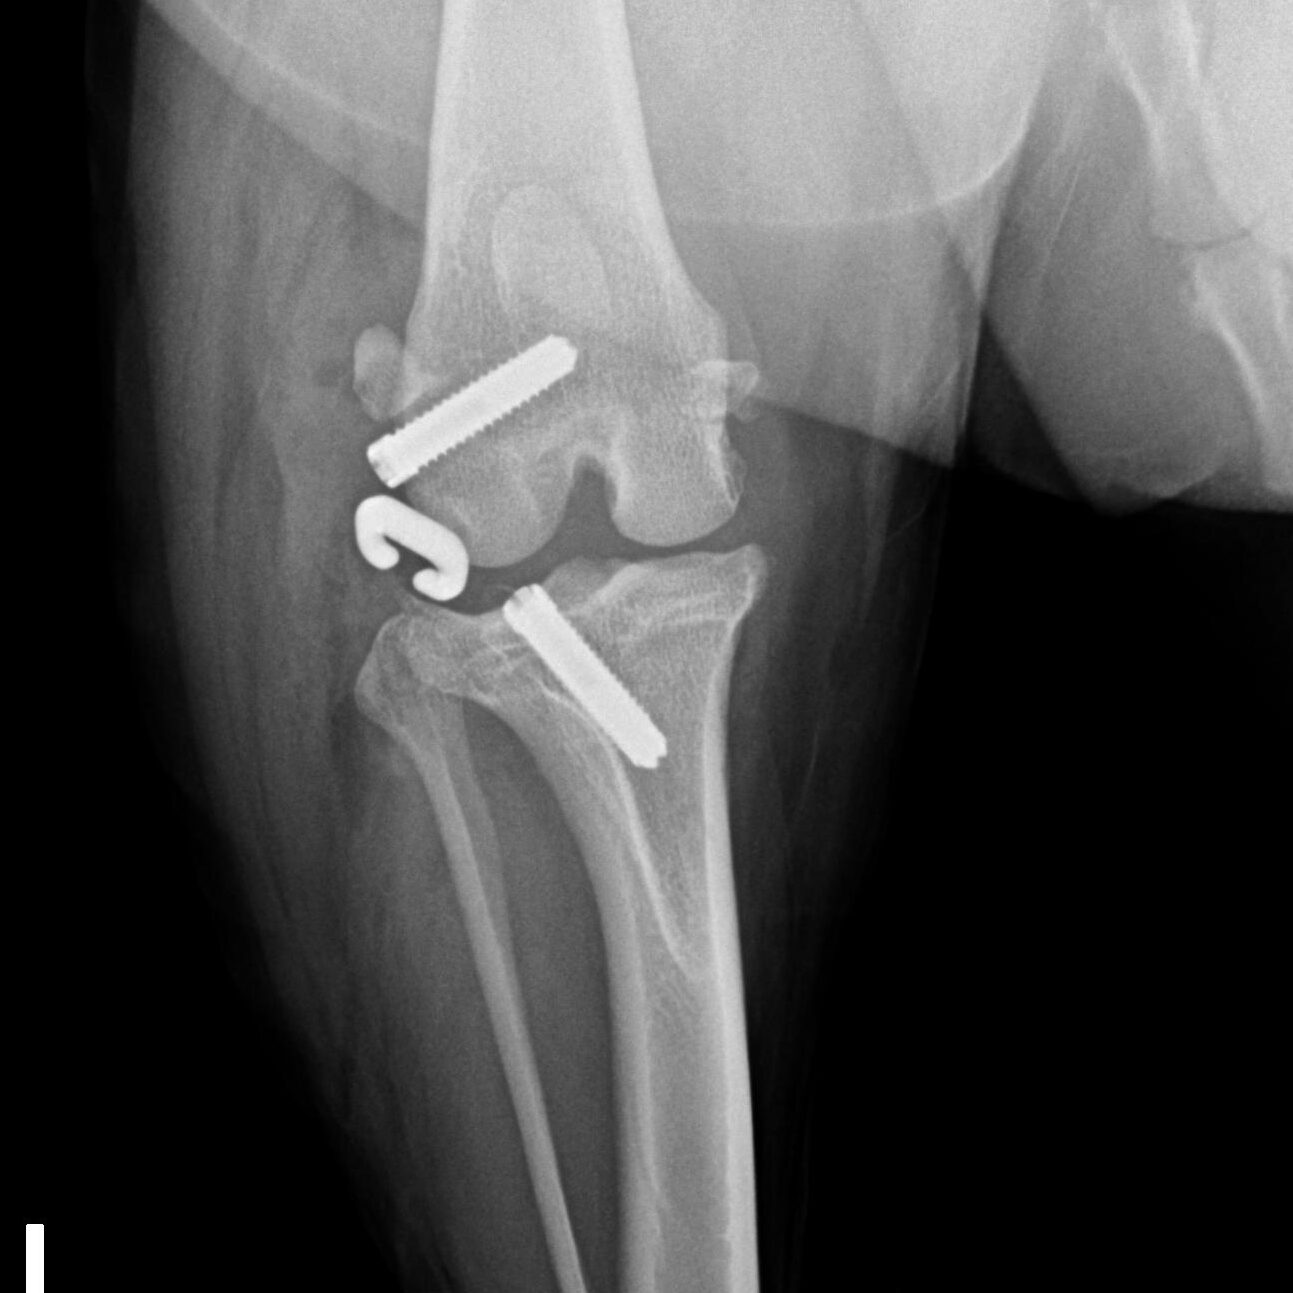

Knochenchirurgie

- Frakturversorgung, Korrekturosteotomie, u.a., verschiedenste Methoden wie Fixateur externe, interne Implantationen von Drähten, Nägeln, Schrauben, Platten inklusive SOP u.a.

Gelenkchirurgie inklusive Arthroskopie

- Kreuzbandriss, Meniskusläsionen, Patellaluxation, laxe Schulter, Isolierter Processus anconaeus, Fragmentierter Processus coronoideus, Osteochondrosis dissecans, Luxationen, Frakturen u.a.